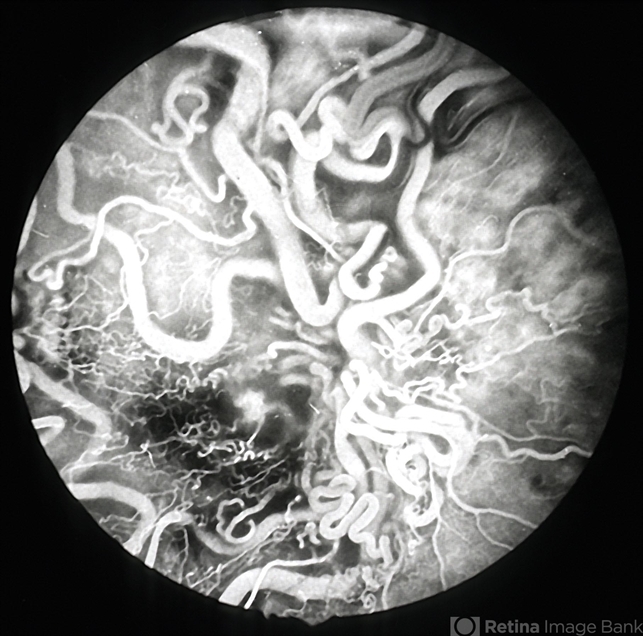

- Retinal AVM

- retinal arteriovenous malformations

- Imaging device

- Fundus camera

- Retinal arteriovenous malformation - Archer group 3 - fluorescein angiogram 2 of 4.